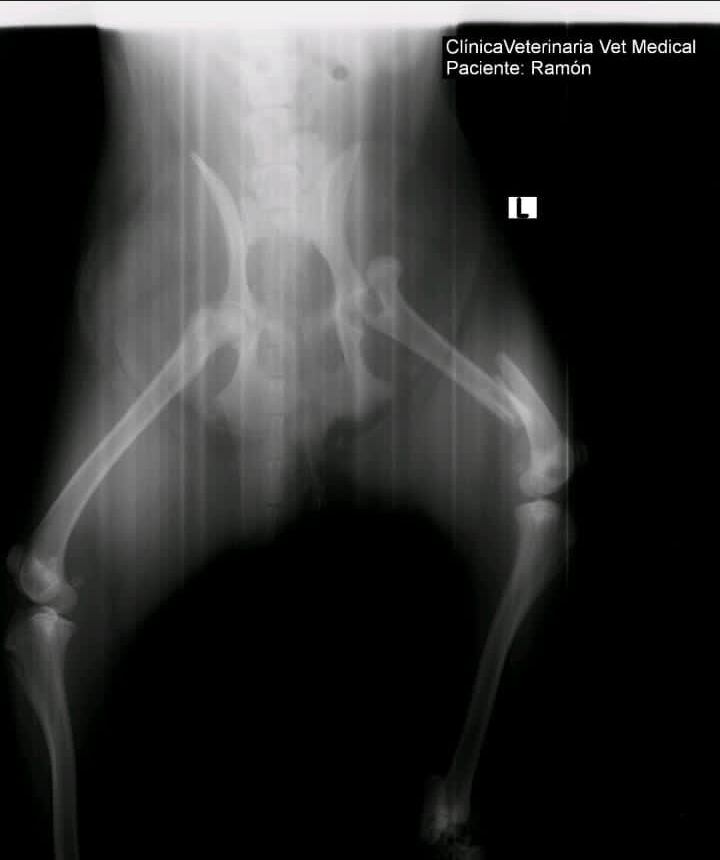

“Ahorita estoy de vacaciones, lejos de mi pueblo, de mi casa y a mi perrito me lo atropellaron ayer (jueves) en horas de la tarde, le causaron varias fracturas en una de sus patas y ahorita estamos hablando con la veterinaria para saber qué sigue”, contó.

Madrigal nos contó que Ramón va a necesitar al menos tres operaciones porque una de sus patitas quedó muy maltratada, esto les saldría en un costo aproximado de un millón de colones y de momento no tienen esa cantidad y la idea es que el perrito no siga sufriendo.